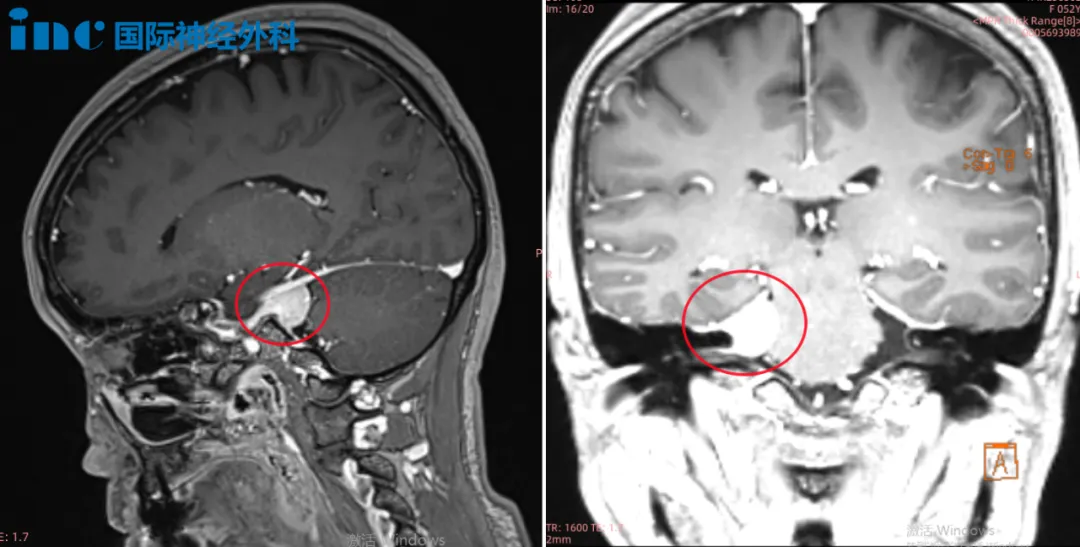

手术情况:2022年巴教授中国行中,成功主刀手术肿瘤全切,无新发神经功能损伤。术后一天ICU查房,钟女士状态清醒,和教授交流顺畅。术后五天查房,钟女士状态良好,连声感谢巴教授并和教授开心合影。病理结果脑膜瘤WHOI级,良性预后很好,术后将不再需要反复放化疗,她可以像正常人一样生活。

▼术前术后MRI对比

钟女士早已恢复了正常生活,术后进行定期的影像随访。术后九个月时,钟女士收到了巴教授回复的随访邮件,没有复发、无残留。